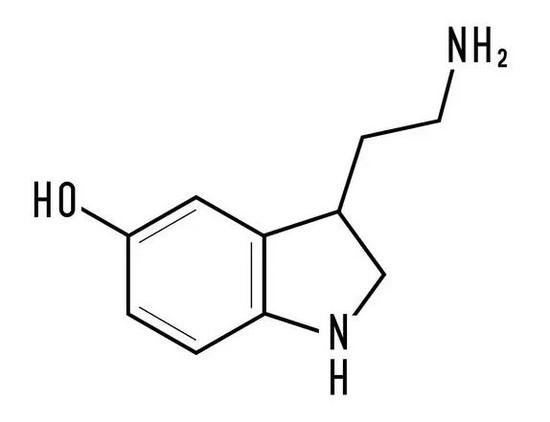

早在六年前,哥本哈根大学的教授让佩里特和他的团队就曾经发表过一项研究,揭示了一个重要的脑神经递质 —— 五羟色胺,又称血清素,在决定机体耐力和中枢性疲劳中的作用。

所谓“中枢性疲劳”指的是在锻炼后,大脑感到疲劳,而不是由于肌肉的状态而感到疲劳。

Via:google

当人们在运动的时候,大脑中的血清素水平会升高,促使人们产生良好的情绪状态,继续进行运动。

但是随着血清素在大脑内的积累,血清素会产生负面的效果,很可能导致中枢性疲劳,就过犹不及了。